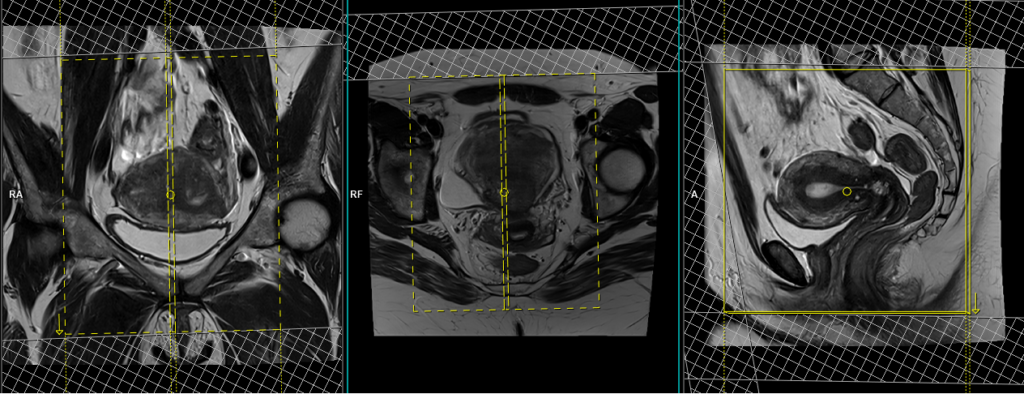

T2 tse sagittal 3mm SFOV

Plan the sagittal slices on the axial plane and angle the positioning block parallel to the line along the linea alba and median sacral crest. Verify the positioning block in the other two planes. In the coronal plane, an appropriate angle must be given, which should be parallel to the lumbosacral spine. Make sure that the slices cover the entire pelvis from the right acetabulum to the left acetabulum. The field of view (FOV) should be sufficiently large to encompass the entire pelvis, typically ranging from 270mm to 300mm. To minimize artifacts caused by arterial pulsation, peristalsis, and breathing, consider adding saturation bands on top and in front of the sagittal block. Ensure an adequate level of phase oversampling to prevent any wrap-around artifacts.

Due to the increased signal-to-noise ratio (SNR) in new generation scanners, motion artifacts can be significant when acquiring images in the anterior-posterior phase direction. This is primarily attributed to the movement of abdominal fat, which exhibits higher signal intensity and can cause ghosting effects over the sagittal images. Therefore, to mitigate this issue, scans are typically performed using a head-to-feet phase direction.

Parameters

TR 3000-4000 | TE 100-120 | SLICE 3 MM | FLIP 130-150 | PHASE A>P | MATRIX 320X320 | FOV 270-300 | GAP 10% | NEX(AVRAGE) 4 |